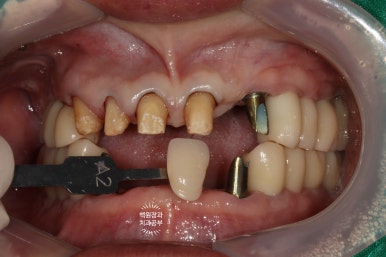

정면에서 찍어본 구강 내 사진 소견입니다.

다수의 치은연상치석, 치은연하치석이 침착되어 있고, 만성치주염으로 인해 치아가 제 위치를 상실하여,

치아의 병적이동 (pathologic migration)을 하고 있는 중이었죠.

풍치가 심해서 만성치주염을 오래 앓으신 분들은 치아 사이가 벌어져 심미적으로 불리한 모습을 많이 보이십니다.

게다가, 어금니들도 씹는 면끼리 물리지 못해서 이제 식사도 어려우신 상황이었어요.